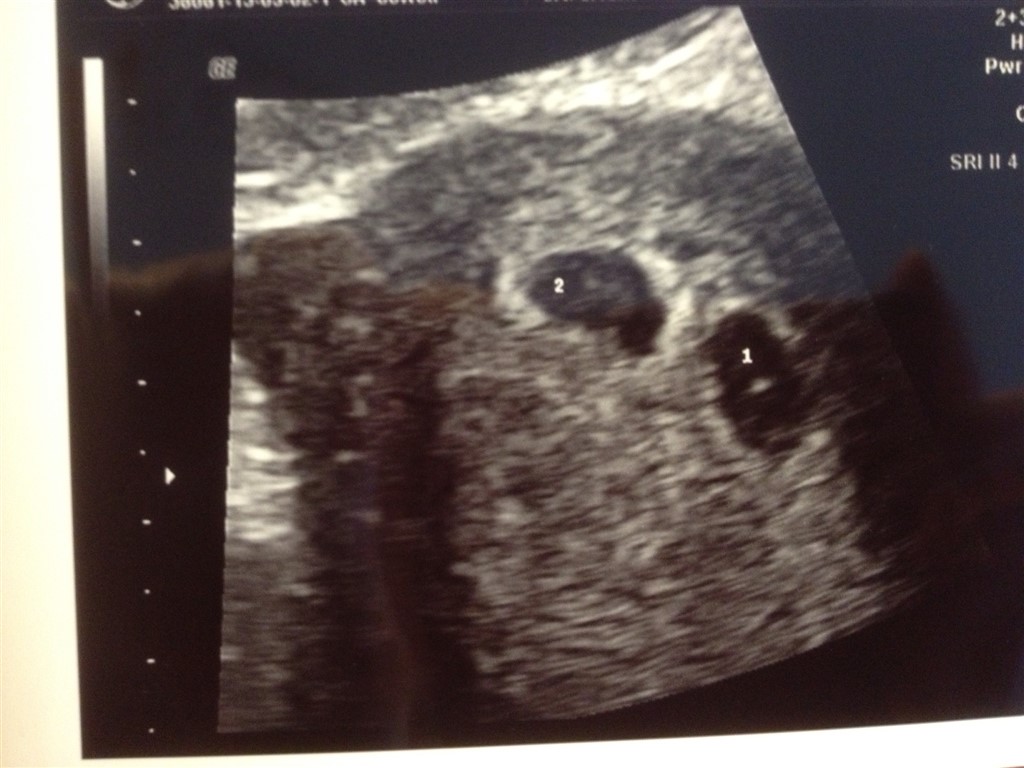

Da jeg til en tidlig scanning fik at vide, at der var to, bad jeg lægen om at finde en anden scanner, for jeg mente bestemt, at den han brugte var defekt

Derefter bad jeg om en second opinion, og først da sygeplejersken havde vist mig på skærmen 3 gange, at der rent faktisk var to, overgav jeg mig - jeg tror dog, at jeg mindst ti gange fik sagt noget i stil med "vi får altså ikke tvillinger i min familie".